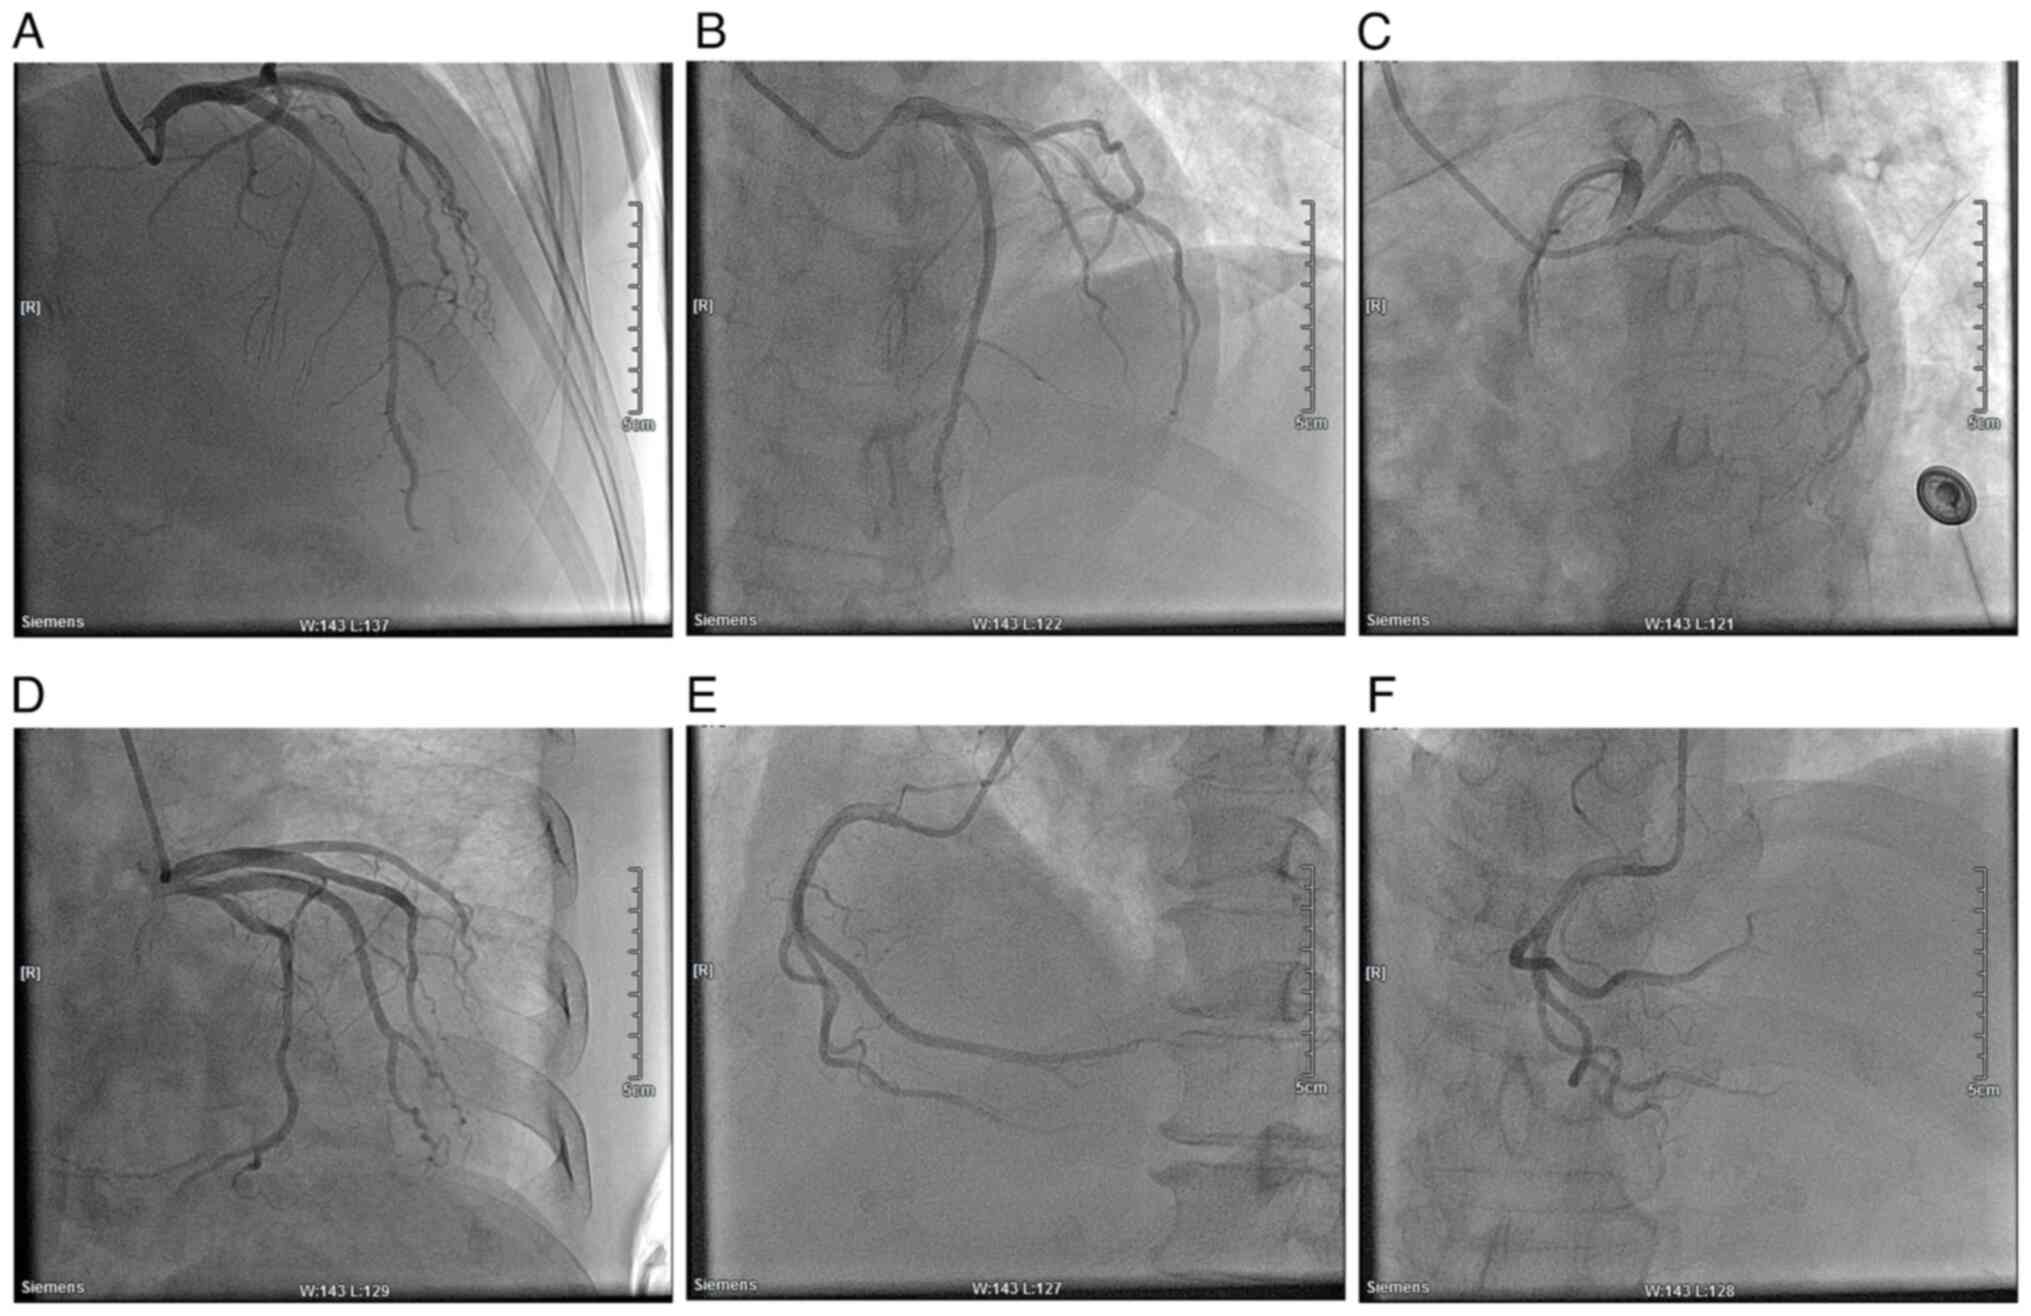

Coronary angiography combined with stenting was proposed on Day 4

significant myocardial infarction (Fig. 6). Cardiac angiography showed that

there was no stenosis in the left main stem, 40% stenosis in the

middle of the left anterior descending branch, and no significant

stenosis in the echogenic branch (Fig.

7). The right crown was thick and smooth with no narrowing.

Based on the results of the electrocardiogram, cardiac enzyme

levels and a history of immunosuppressant medication, immune

myocarditis was considered. The patient was treated with hormone

| Figure 7Cardiac angiography of the patient.

(A) RAO, 30˚ and CRA, 30˚. (B) LAO, 30˚ and CRA, 20˚. (C) LAO, 45˚

and CRU, 20˚. (D) RAO, 30˚ and CAU, 20˚. (E) LAO, 45˚. (F) CRA,

30˚. RAO, right anterior oblique; CRA, cranial; LAO, left anterior

oblique; CRU, caudal. |